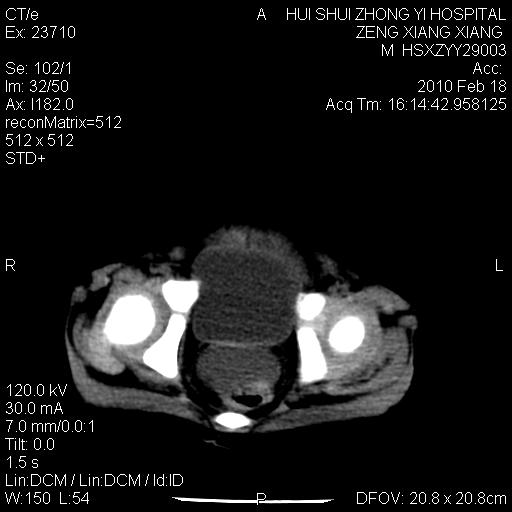

标题: PED3106:男,2岁,腹胀1月。 [打印本页]

标题: PED3106:男,2岁,腹胀1月。

定位腹膜后,肾上腺来源;

定性:恶性神经源性,肾上腺神经节母细胞瘤可能性大。

鉴别:肝母、肾母、肝脏中胚层错构瘤。

依据:年龄、有钙化,肾脏及肝脏受压移位。

肝母细胞瘤可能性大,右肾形态大体可见,不支持肾母细胞瘤,右肾移位不明显,肾上腺神经母细胞瘤可能性不大。